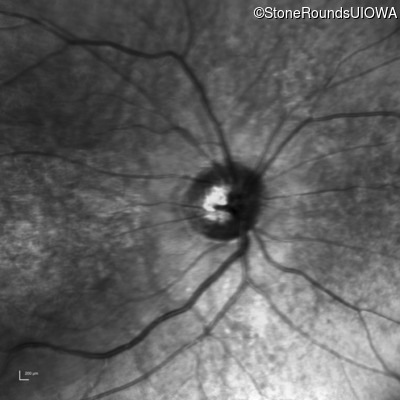

Infrared Fundus Photograph - Right - 20/500

Exemplar